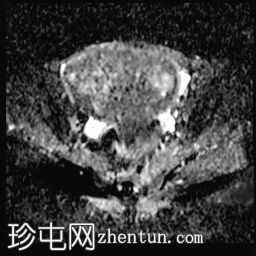

3.jpg

轴向

T1厚度

子宫后壁可见一个边界清晰、体积较大的浆膜下肌瘤,大小约为16.1 x 10.5 x 14.4 cm(宽 x 深 x 高)。

该肌瘤在T1加权像上呈中等信号,在T2加权像上呈低信号,内部区域呈囊性变性。

该肿块导致正常子宫结构严重变形。增强扫描显示轻度不均匀强化,未见弥散受限征象或提示恶性肿瘤的可疑强化。